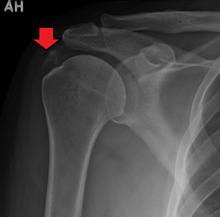

A plain X ray of the shoulder showing calcific tendinitis | |

The calcific deposits are visible on X-ray as discrete lumps or cloudy areas. The deposits look cloudy on X-ray if they are in the process of reabsorption, and this is also when they cause the most pain. The deposits are crystalline when in their resting phase and like toothpaste in the reabsorptive phase. However, poor correlation exists between the appearance of a calcific deposit on plain X-rays and its consistency on needling. Ultrasound is also useful to depict calcific deposits and closely correlates with the stage of disease.[1]